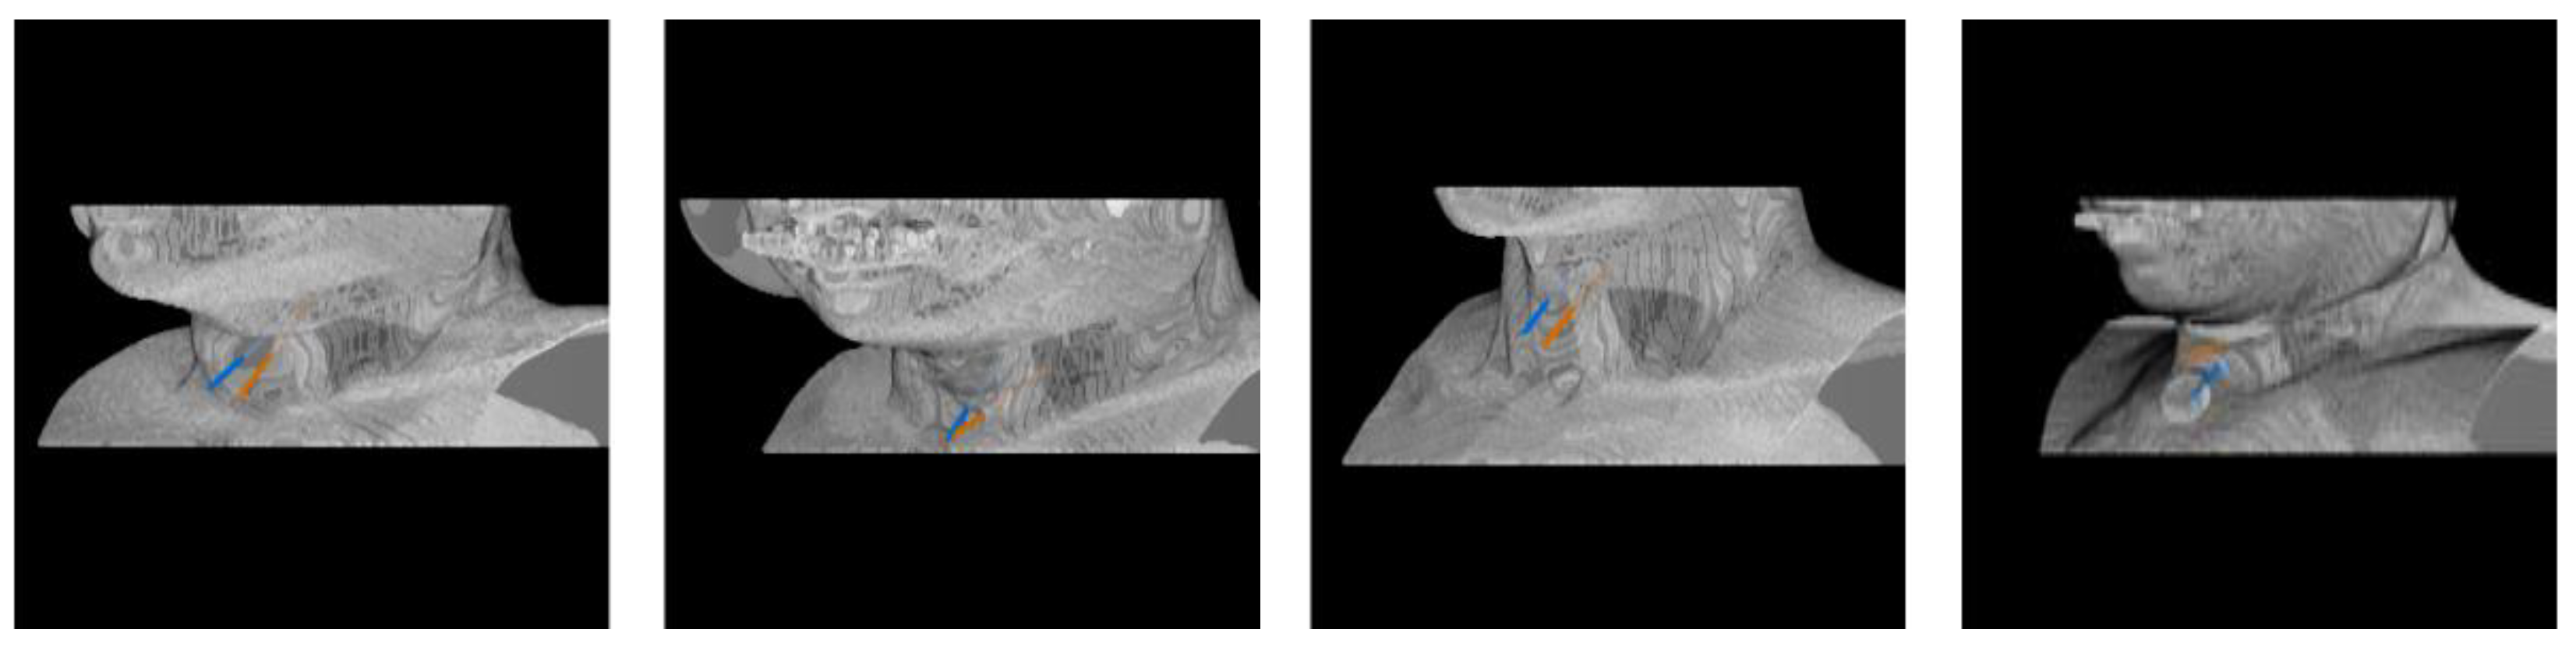

Automatic Needle Route Proposal in Preoperative Neck CT for Injection Laryngoplasty

- We propose the first automatic method to compute the optimal needle route in neck CT for TIL based on critical structure segmentation and minimal cost route search.

2. Methodology

2.4. Optimal Needle Route Search

3. Experimental Results